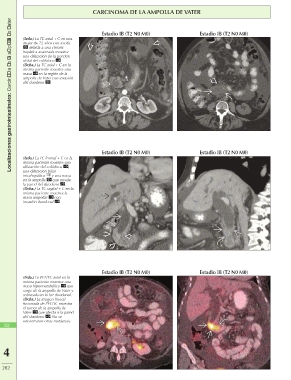

CARCINOMA DE LA AMPOLLA DE VATER

Localizaciones gastrointestinales: Carcinoma de la ampolla de Vater (Izda.) La TC axial + C en una Estadio IB (T2 N0 M0) Estadio IB (T2 N0 M0)

mujer de 72 años con ascitis

debida a una cirrosis

hepática avanzada muestra

una dilatación de la porción

distal del colédoco .

(Dcha.) La TC axial + C en la

misma paciente muestra una

masa en la región de la

ampolla de Vater con invasión

del duodeno .

Estadio IB (T2 N0 M0) Estadio IB (T2 N0 M0)

(Izda.) La TC frontal + C en la

dilatación del colédoco ,

una dilatación biliar

intrahepática y una masa

en la ampolla que invade

la pared del duodeno .

(Dcha.) La TC sagital + C en la

misma paciente muestra la

masa ampollar con

invasión duodenal .

(Izda.) La PET/TC axial en la Estadio IB (T2 N0 M0) Estadio IB (T2 N0 M0)

masa hipermetabólica que

surge de la ampolla de Vater y

sobresale en la luz duodenal.

(Dcha.) La imagen frontal

fusionada de PET/TC muestra

el tumor de la ampolla de

Vater que afecta a la pared

del duodeno . No se

encontraron otras metástasis.